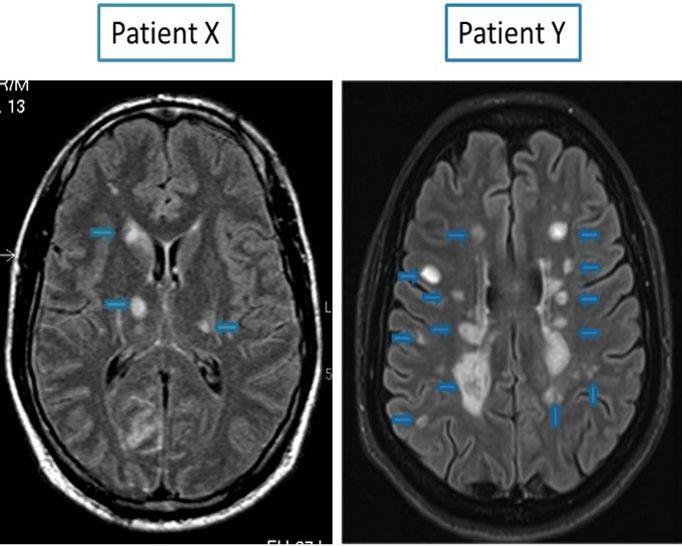

IRM de suivi de SEP interprétation assistée par technique de soustraction longitudinale

IRM cérébrales et médullaires pathologiques dans le cas d'une SCLEROSE EN PLAQUE — Site des. Dans ces conditions, il est le plus souvent proposé. Il n'y a pas d'examens spécifiques au diagnostic de la SEP